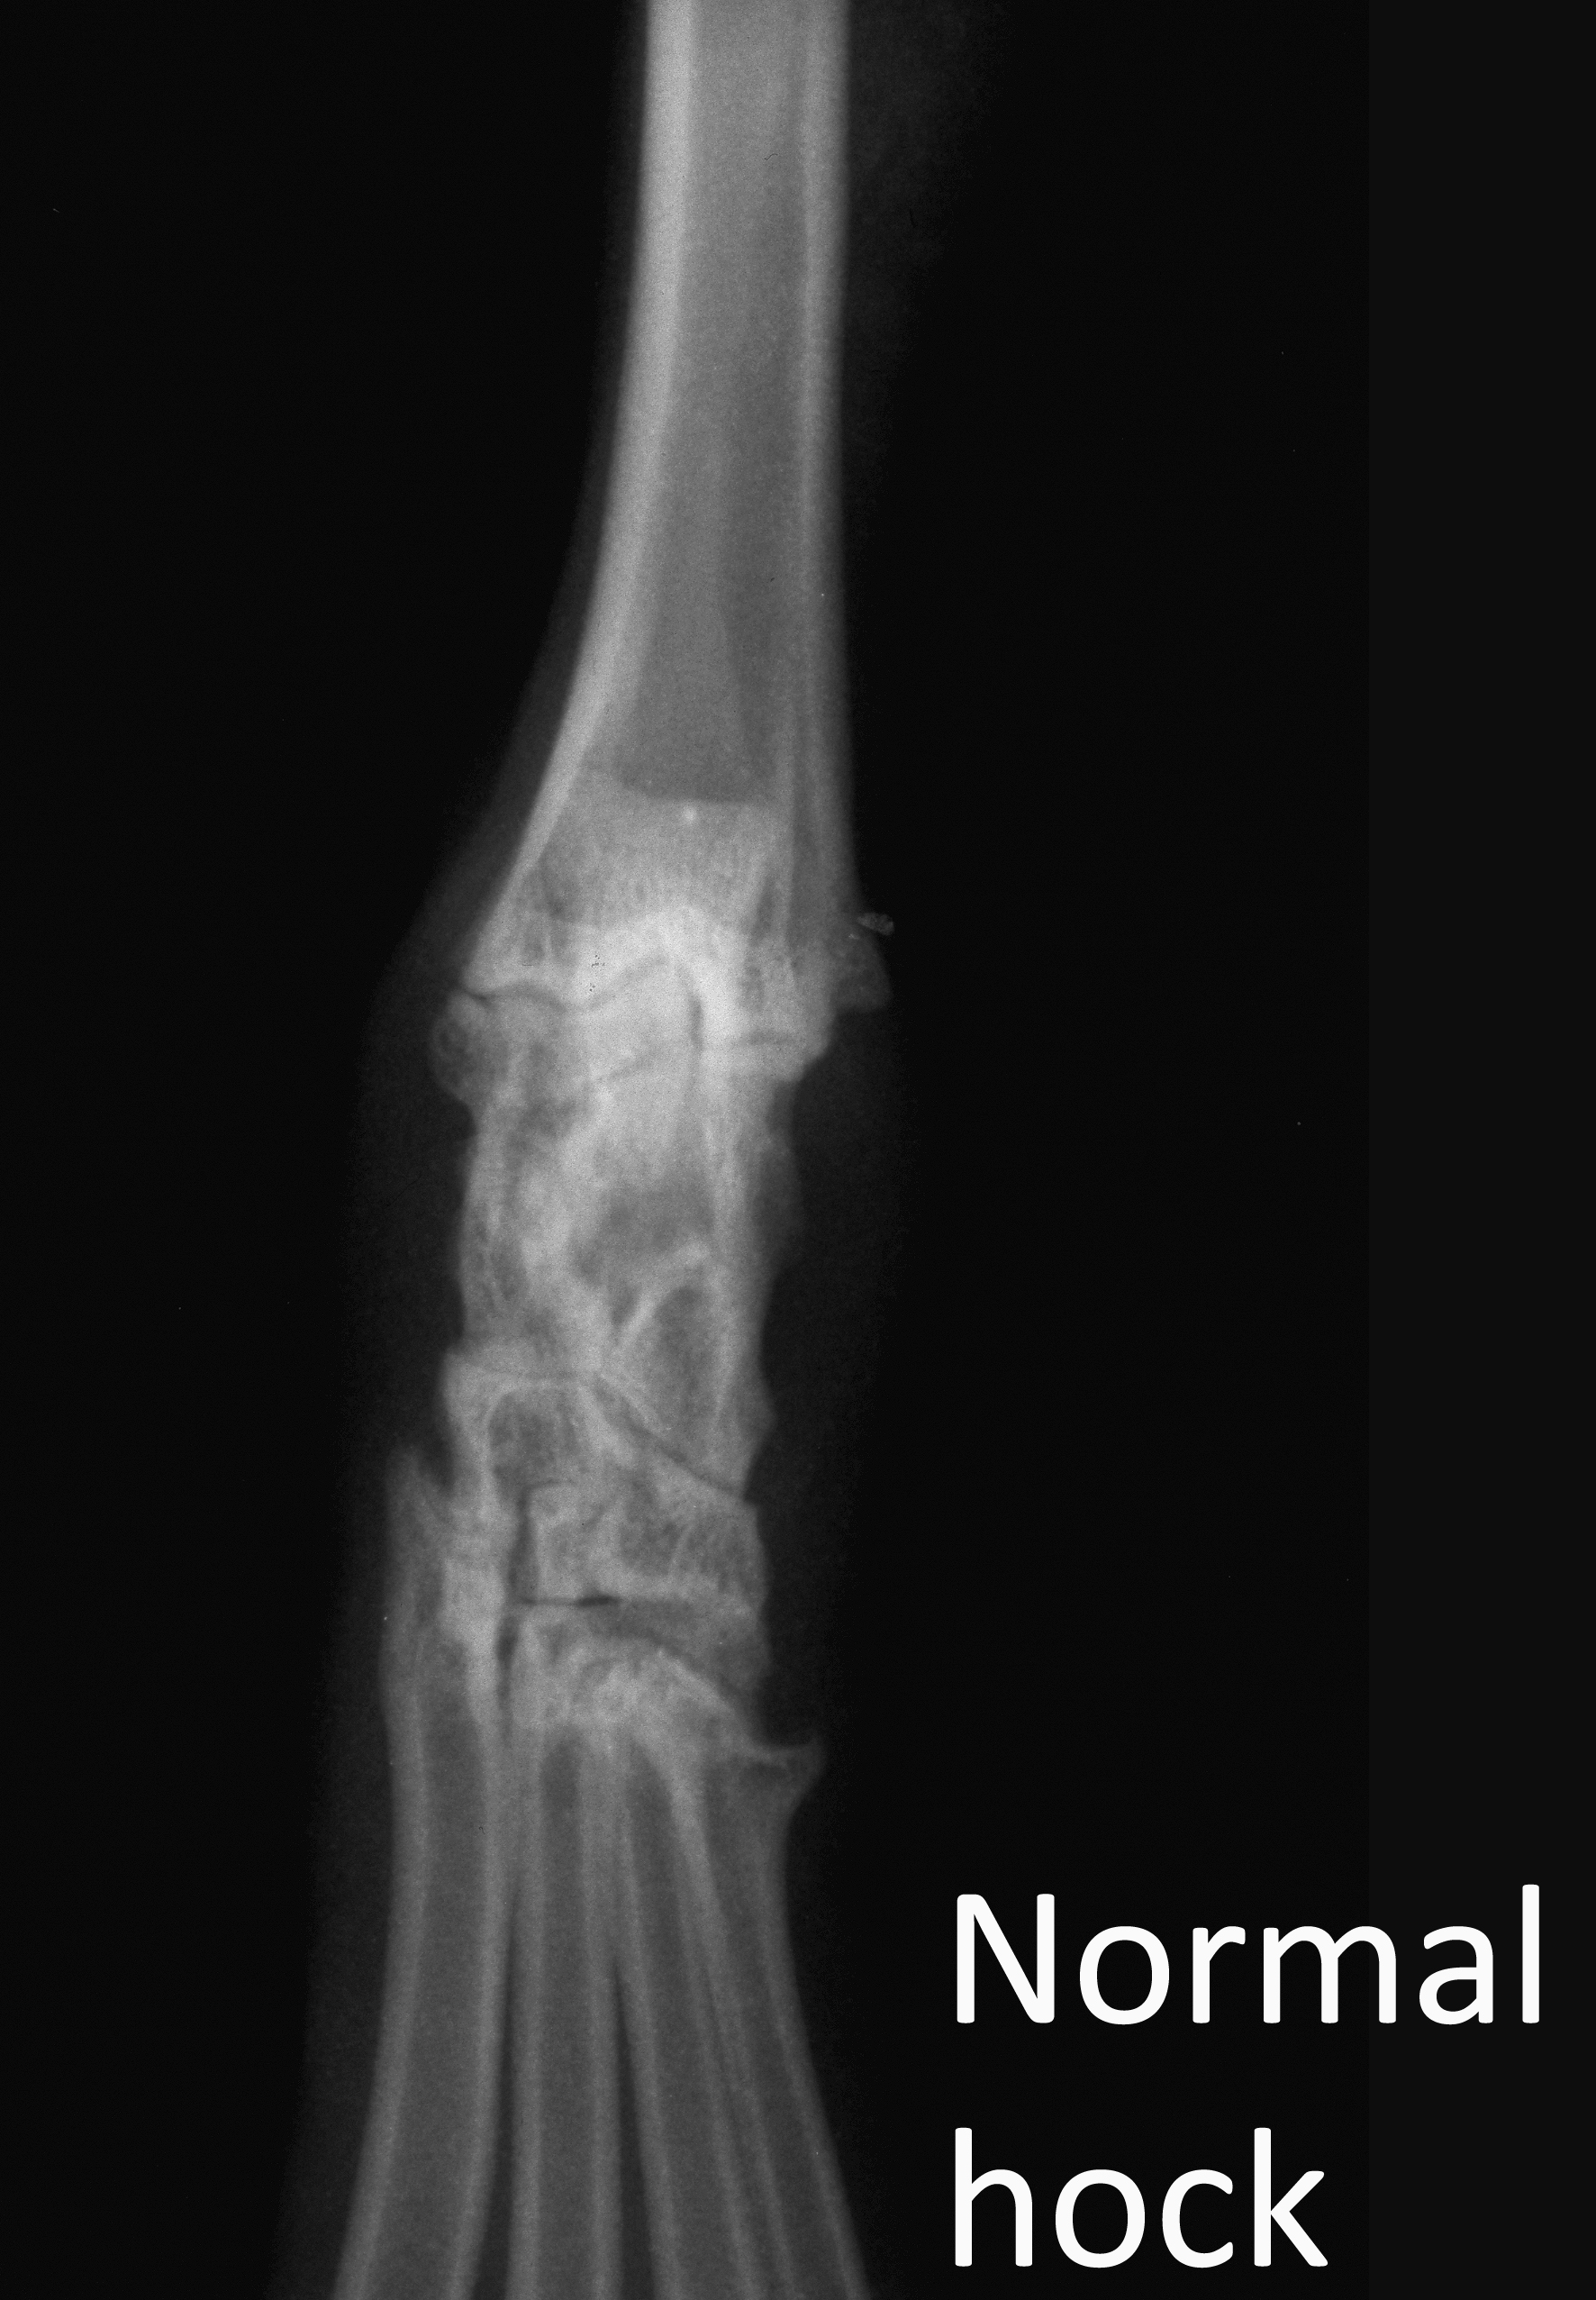

Normal hock vd

Radiograph

Orthopaedics